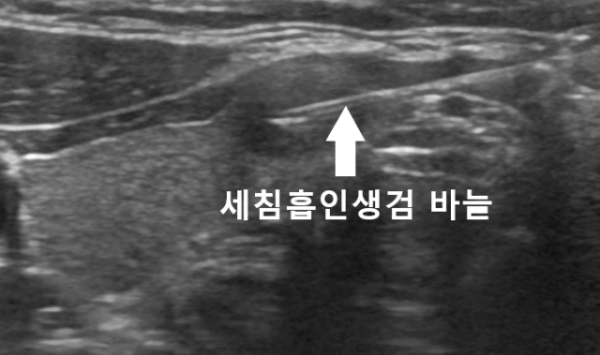

조직검사로 확인이 필요할 것으로 판단되어 이에대한 설명을 드린후 동의하셔서 내원당일에 바로 세침흡인검사를 시행하였습니다.

간단한 부분마취후에 안전하게 세침흡인검사를 시행하였으며 2일만에 최종결과를 확인하였습니다.